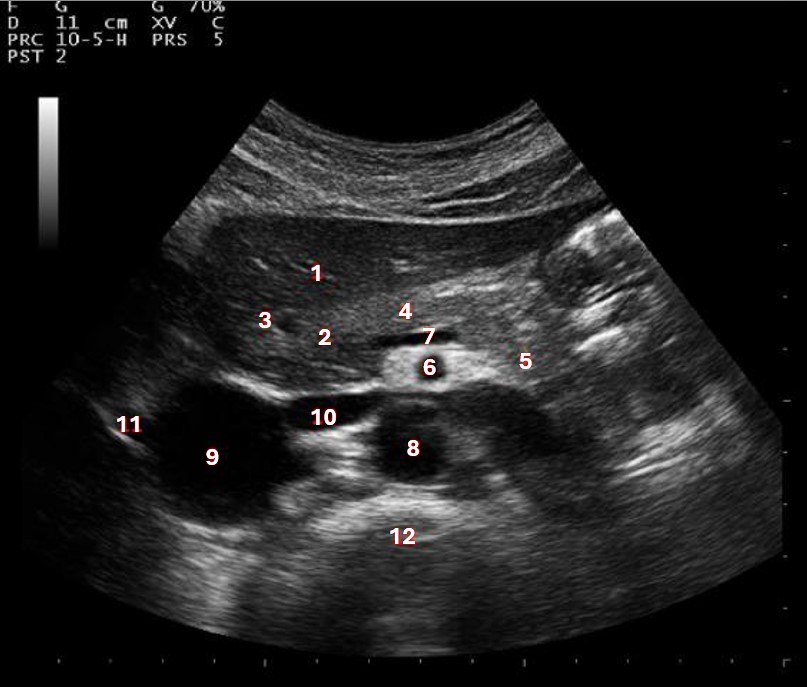

Which of the following structures is labeled #5?

lateral left lobe |

What lobe of the liver is indicated by #1?

posterior right lobe

What structure/vessel is indicated by #8?

medial left lobe |

What lobe of the liver is indicated by #2?

anterior right lobe |

Which of the following structures is labeled #1?

Which of the following structures is labeled #7?

anterior right lobe |

What structure/vessel is indicated by #12?

spine

Which of the following structures is labeled #6?

medial left lobe |

Which of the following structures is labeled #3?

IVC

Which of the following structures is labeled #8?

posterior right lobe |